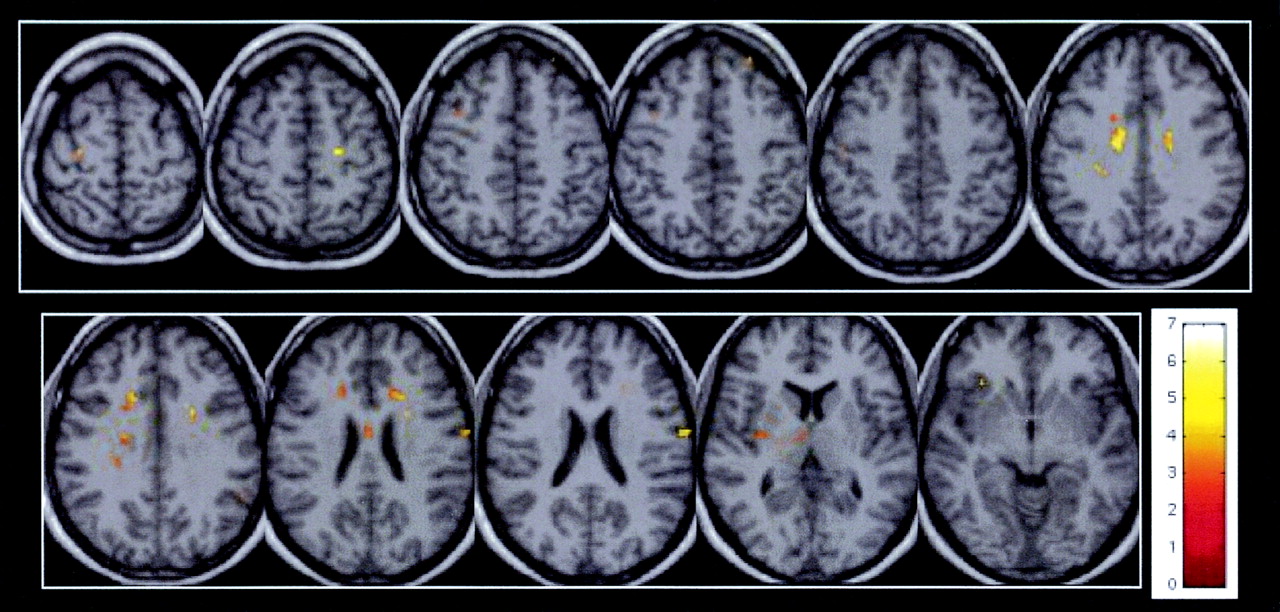

Correlation Between Brain MTR and TMTA Score

Significant correlations between MTR and TMTA scores (Spearman rank test, P < .05) were observed in the gray matter of patients inside the bilateral BA4, bilateral BA40, bilateral BA3, left BA8, right lateral sulcus, right BA6, and right claustrum (Fig 2 and Table 4). Correlations were also found in the white matter involving the body of corpus callosum, bilateral cingulum, left frontal white matter, and left occipitofrontal fascicles.

In patients with CISSMS, significant correlations between MTR and TMTA scores (Spearman rank test, P < .05) are observed inside the bilateral BA4, bilateral BA3, right BA6, left BA8, left frontal white matter, left occipitofrontal fascicles (top row, left to right) and in the left frontal white matter, left occipitofrontal fascicles, body of corpus callosum, bilateral cingulum, bilateral BA40, right lateral sulcus, and right claustrum (bottom row, left to right).

Spearman rank correlation test between local MTR and functional scores in patients with CISSMS